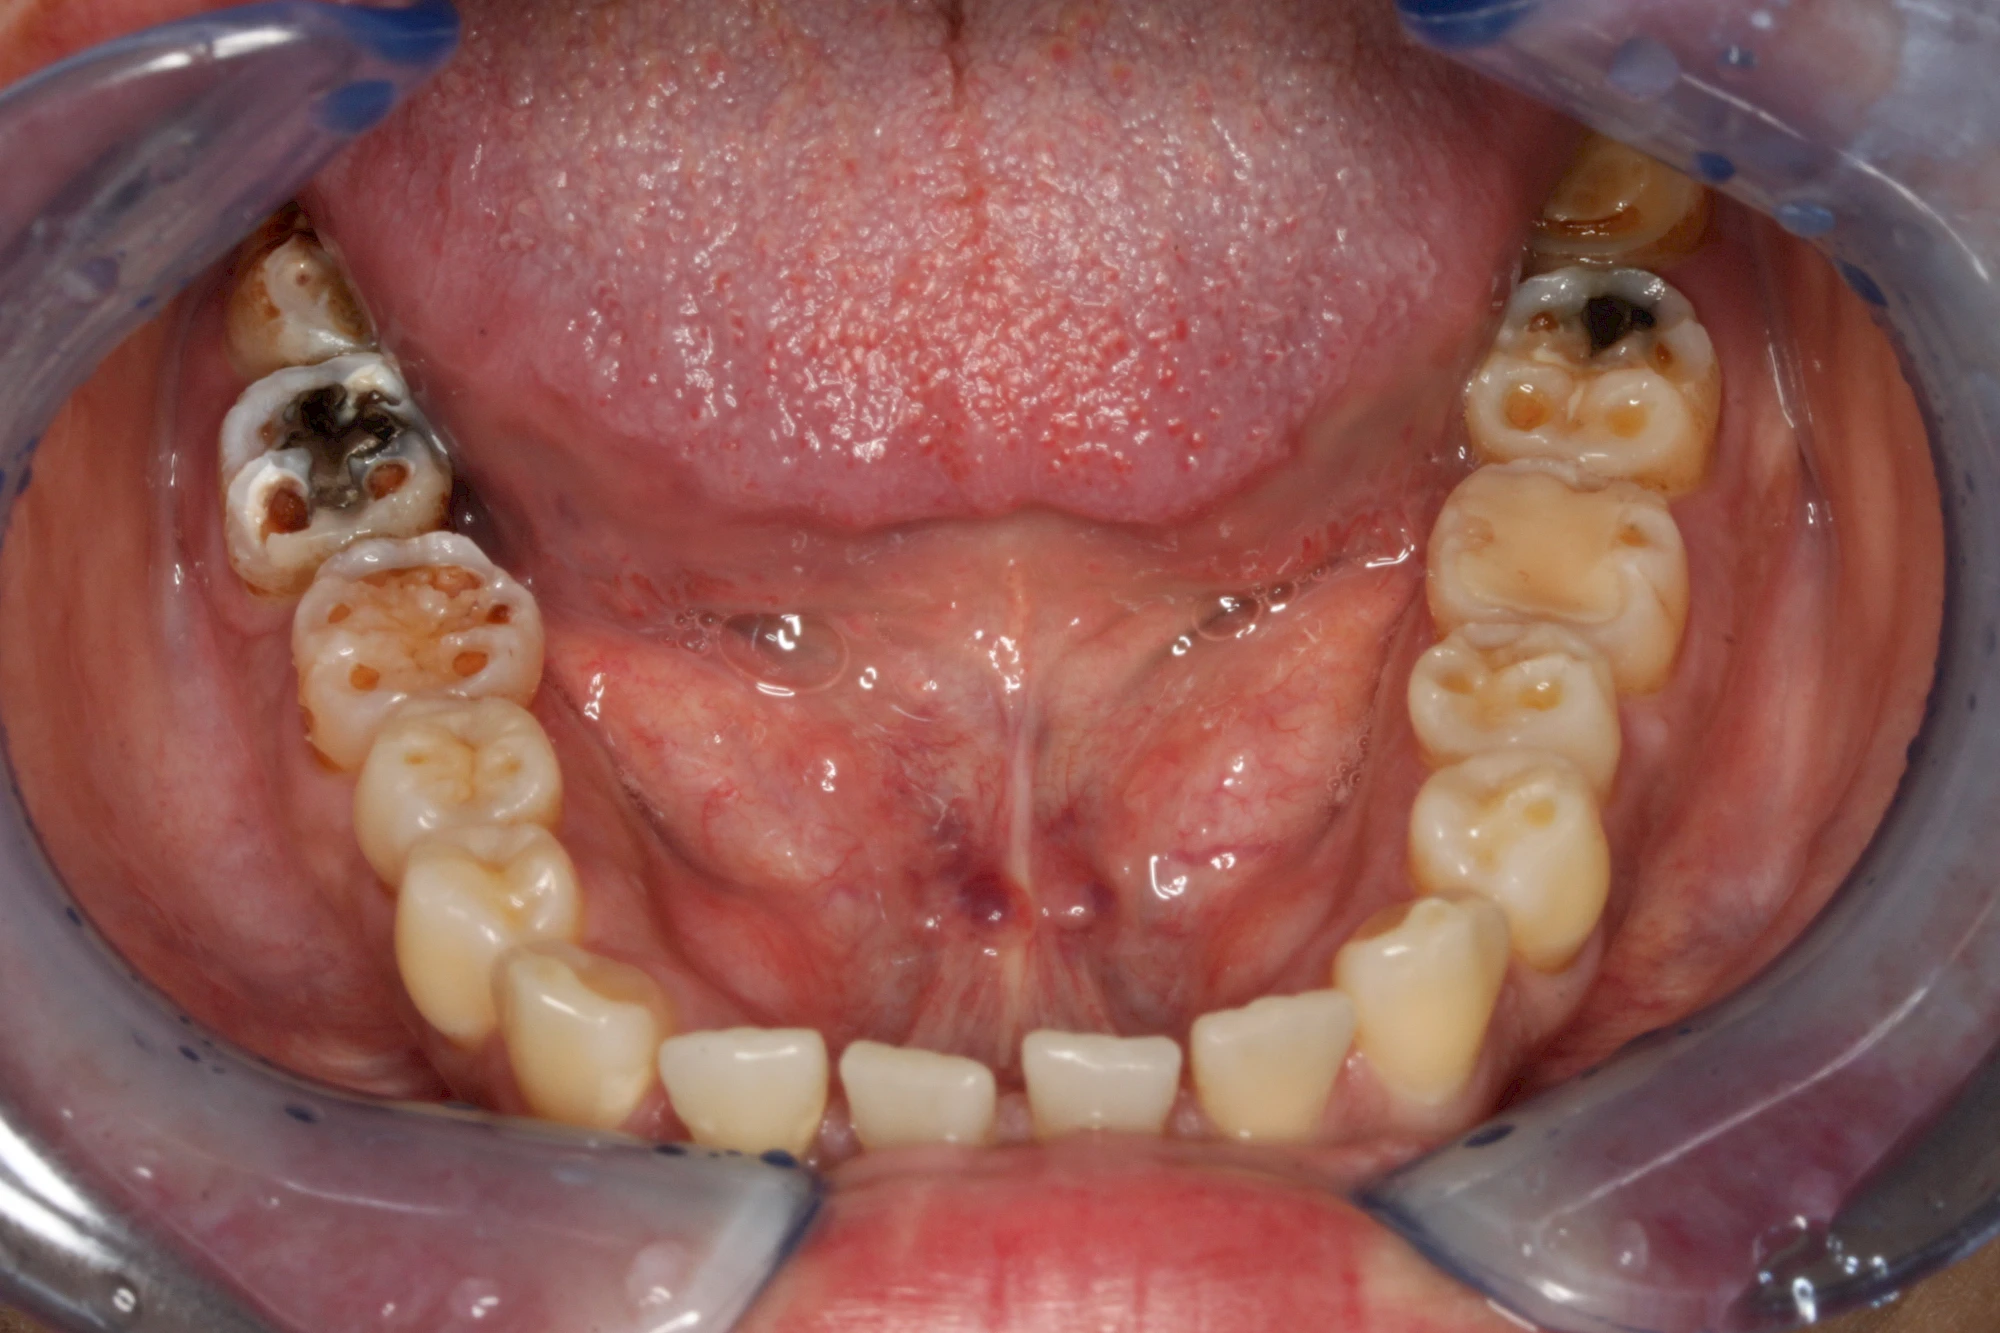

Über die Zeit können verschiedene Prozesse die Zahnhartsubstanzen aufzehren:

- Abnutzung durch Kauen (Abrasion) oder duch durch übermäßiges Knirschen bzw. Pressen (Attrition)

- Säurebedingte Auswaschung (Erosion)

- Knirschen bzw. Pressen und ungünstige Putztechnik (Druck): keilförmige Defekte

Die Zähne können dabei auf Reize (warm, kalt, süß, sauer) oder auch beim Zähneputzen empfindlich oder schmerzhaft sein. In allen diesen Fällen ist es sinnvoll, den Zahnarzt zu kontaktieren und das weitere Vorgehen abzustimmen.